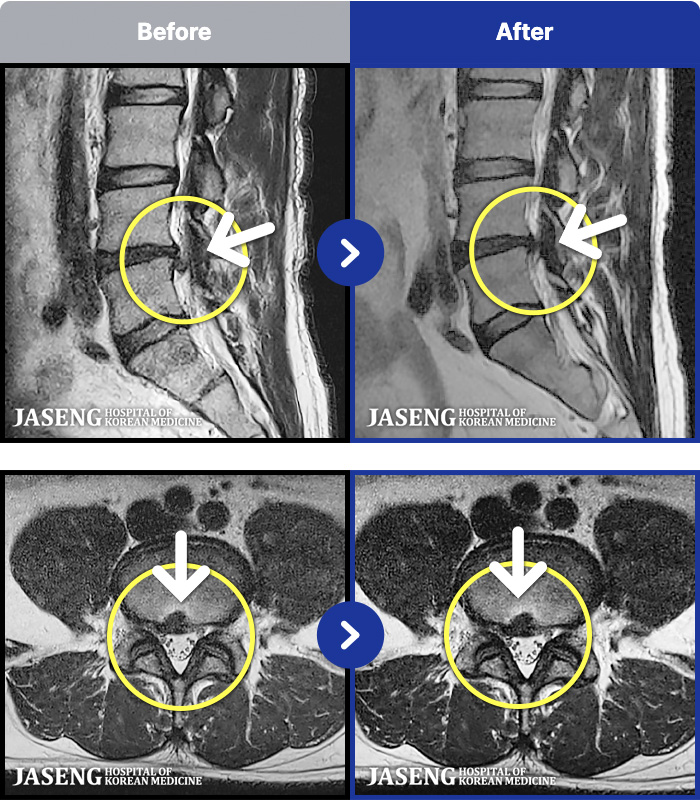

[뱸] 19.11.28~25.05.06